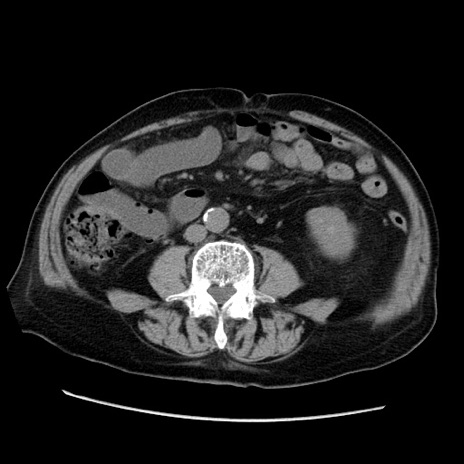

冠状断像

症例21(横断像)

【症例】70歳代男性

【主訴】腹痛

【現病歴】肝硬変・肝細胞癌にてかかりつけの方。約9時間前に食後より腹痛出現。症状が徐々に増悪し、嘔吐出現したため来院。

【既往歴】肝硬変、肝細胞癌(RFA、TACE後)

【身体所見】意識清明、表情苦悶様、BT 36℃、BP 129/78mmHg、P 88bpm、SpO2 97%(RA)、右上腹部から心窩部にかけて圧痛あり、反跳痛なし、筋性防御あり。

【データ】WBC 5800、CRP 0.16